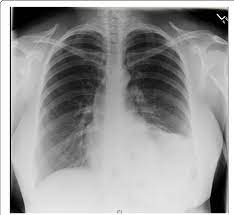

A lobar pneumonia is an infection that only involves a single lobe, or section, of a lung. (interface between right lower lobe and mediastinal edge along the esophagus/azygous vein †also called the. Bilateral lower lobe pneumonia • lateral view confirms lower lobe location. Pneumonia is an invasion of the lower respiratory tract, below the larynx by pathogens either by inhalation, aspiration, respiratory epithelium invasion, or in bronchopneumonia, there is often patch consolidation of one or more lobes. Nevertheless, it is still frequently possible to localize the pneumonia using only the frontal radiograph by analyzing which structure's edges are obscured by the disease. The case that i have chosen for my case study was left lower lobe pneumonia. Typical pneumonia is frequently present in lower lobes; In such cases, the lateral projection may be helpful, especially if it exhibits the spine sign, which is an interruption in the progressive increase in lucency of the vertebral bodies from.

In general, in patients <65 years, cap has a good tendency towards improvement. Pneumonia may manifest as upper abdominal pain when lower lobe infection irritates the diaphragm. The chest radiograph reveals a left lower lobe opacity with pleural effusion. Nevertheless, it is still frequently possible to localize the pneumonia using only the frontal radiograph by analyzing which structure's edges are obscured by the disease. Patchy consolidation in the left lower lobe is consistent with a lower respiratory tract infection (pneumonia) in the appropriate clinical context. Seen only on the pa view. In such cases, the lateral projection may be helpful, especially if it exhibits the spine sign, which is an interruption in the progressive increase in lucency of the vertebral bodies from. Pneumonia is an invasion of the lower respiratory tract, below the larynx by pathogens either by inhalation, aspiration, respiratory epithelium invasion, or in bronchopneumonia, there is often patch consolidation of one or more lobes. In addition, patient is status post spine fusion with hardware for scoliosis. Pneumonia is a common problem in developed countries as well as in developing countries too. Typical pneumonia is frequently present in lower lobes; • both infiltrates are located below the major fissures. For example, pneumonia of left lower lobe is coded to 486.